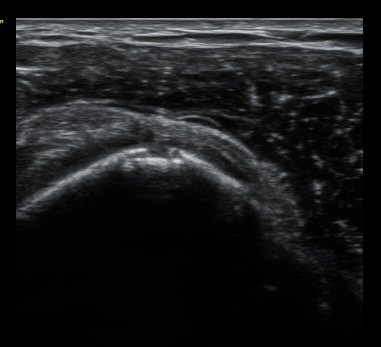

ÃÊÀ½ÆÄ °Ë»ç

ȸÀü±Ù°³°£°Ý Ⱦ´Ü¸é°Ë»ç¿¡¼­ Á¡¾×³¶³» ¼ö¾×Àú·ù°¡ °üÂûµÈ´Ù(±×¸² 1). ÀÌµÎ¹Ú±Ù°Ç °í¶û¿¡¼­´Â ƯÀÌ ¼Ò°ßÀ» º¸ÀÌÁö ¾Ê´Â´Ù(±×¸² 2). ȸÀü±Ù°³°£°Ý ³»Ãø¿¡¼­ °ß°©ÇϱٰÇÀÇ ÆÄ¿­°ú Á¡¾×³¶³» ¼ö¾×Àú·ù°¡ °üÂûµÈ´Ù(±×¸² 3, 4). ±Ø»ó°Ç Ⱦ´Ü